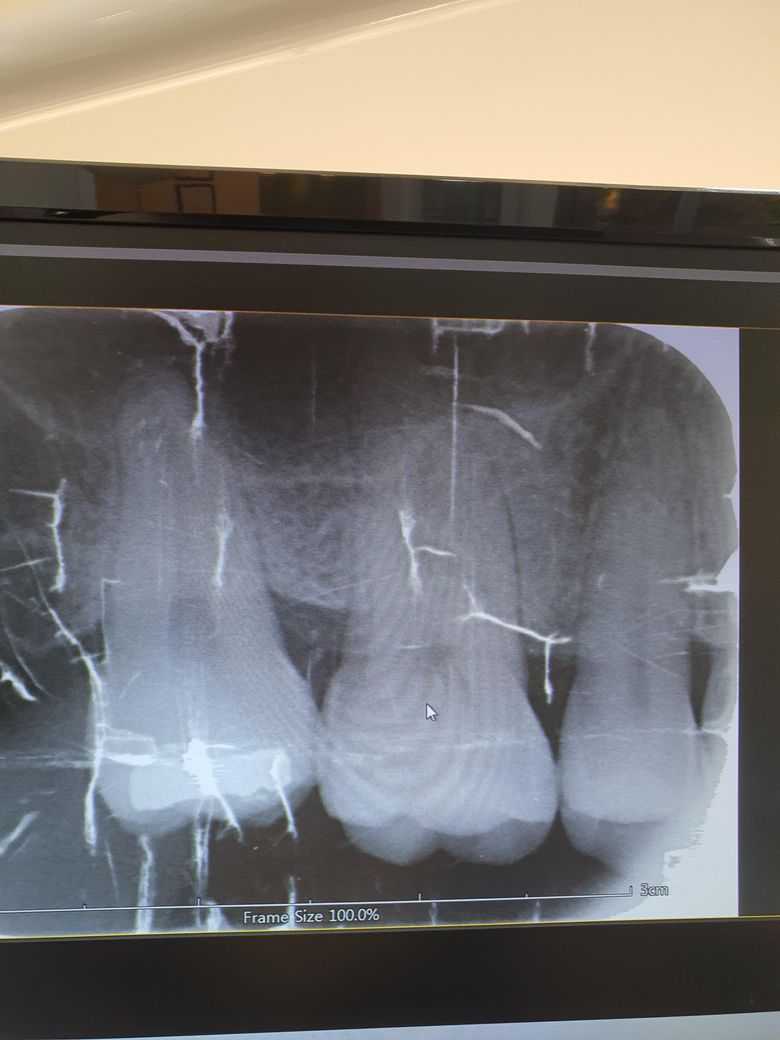

뿌리쪽 치근단 어두운거 이거는 염증인가요?

아래 사진 두번째 어금니요 어금니가 중간에 금이 가있기는한데 뿌리쪽검은색이랬는데 선생님이 말씀도 안하시구 쌔게쳤어요...그때 놀라서못물어봤고 설명도없으시고 다른곳 가버리심ㅜㅜ

사진에 보이는건 상악동이라는 코 옆에 잇는 빈공간입니다. 염증이 아니니 너무 걱정하지마세요.

1. 두번째 어금니 뿌리 주위가 검은 것은 상악동공간과 겹쳐보여 그렇습니다

3. 해당 치아의 뿌리끝으로 염증이 있는지 명확히 보이진 않으나 치아 주위 치주인대 상태가 좋지는 않아보입니다 증상이 있다면 신경치료로 이어질 가능성도 있습니다 증상이 없다면 좀 더 지켜보시죠

사진으로는 정확한 확인이 어려워 보입니다. 해당체 증상이 없거나 방사선 사진에 뚜렷한 병소가 있지 않는다면 크게 문제가 되지 않을 가능성이 높습니다. 치과용 CT를 촬영하게 되면 더 정확한 상황을 알 수 있을 것으로 생각됩니다.